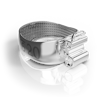

Корректор класса II Вильямса (исполнение 3) - Набор 320-0100

Описание товара

Характеристики